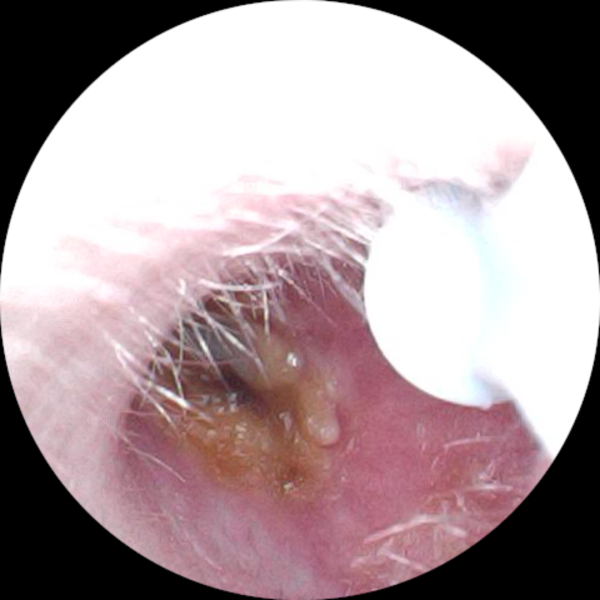

bananaphon · 27/06/2024 19:50

I've had a persistent ear infection over the last month. I've almost finished my third round of drops and one round of amoxicillin this week. No more pain and I can hear about 90% from that ear. I looked inside with my new camera and saw this 🤢 I don't want to dare start digging around as it was so painful the last month and has only just stopped making me feel unwell. I have a follow up gp appointment on 11th July but not sure if I should ask to bring it forward. I've also had micro suction twice in that time!

Used my ear camera